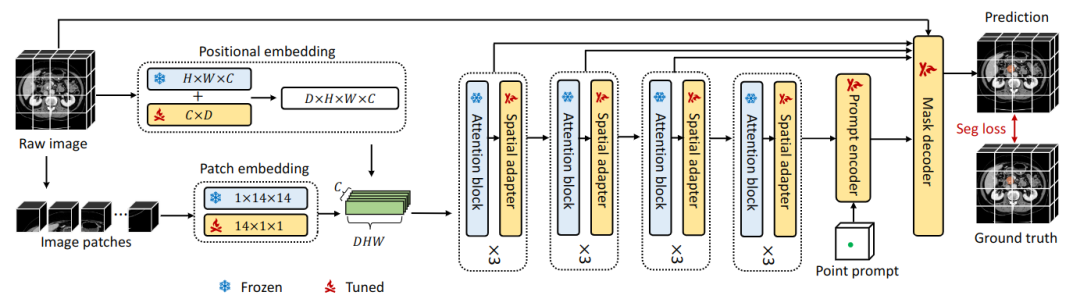

3DSAM-adapter:为了适应3D空间信息,提出了一种修改图像编码器的方案,使原始的2D变换器能够适应体积输入。

Medical SAM Adapter

Medical SAM Adapter:专为SAM设计了一个通用的医学图像分割适配器,能够适应医学数据的高维度(3D)以及独特的视觉提示,如 point 和 box。